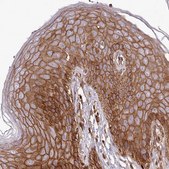

immunohistochemistry: 1:500- 1:1000

All Prestige Antibodies Powered by Atlas Antibodies are developed and validated by the Human Protein Atlas (HPA) project and as a result, are supported by the most extensive characterization in the industry.

The Human Protein Atlas project can be subdivided into three efforts: Human Tissue Atlas, Cancer Atlas, and Human Cell Atlas. The antibodies that have been generated in support of the Tissue and Cancer Atlas projects have been tested by immunohistochemistry against hundreds of normal and disease tissues and through the recent efforts of the Human Cell Atlas project, many have been characterized by immunofluorescence to map the human proteome not only at the tissue level but now at the subcellular level. These images and the collection of this vast data set can be viewed on the Human Protein Atlas (HPA) site by clicking on the Image Gallery link. We also provide Prestige Antibodies® protocols and other useful information.

• IHC tissue array of 44 normal human tissues and 20 of the most common cancer type tissues.